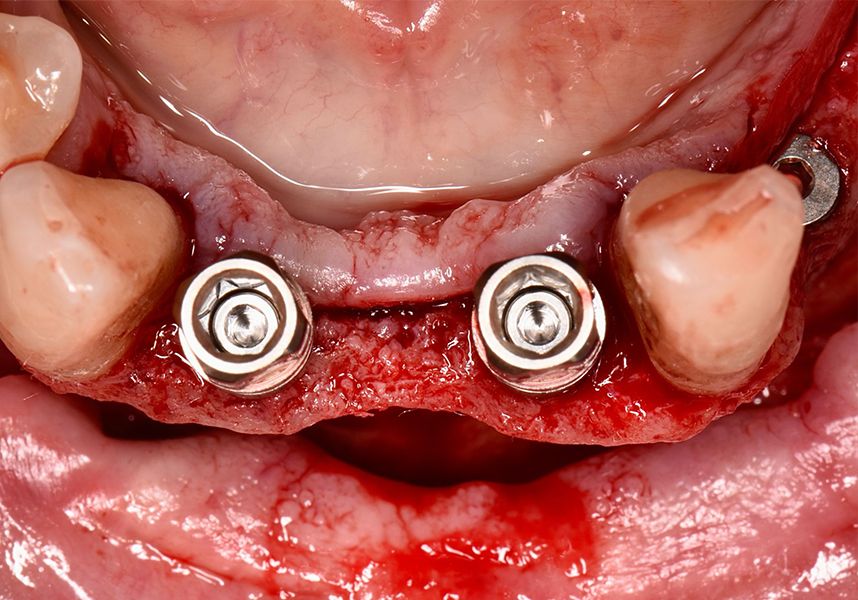

After a post-operative period without complications, the healing abutments were fitted in a second surgical stage 5 months later. Six months after implant placement, the final metal-ceramic prosthetic restoration was loaded.